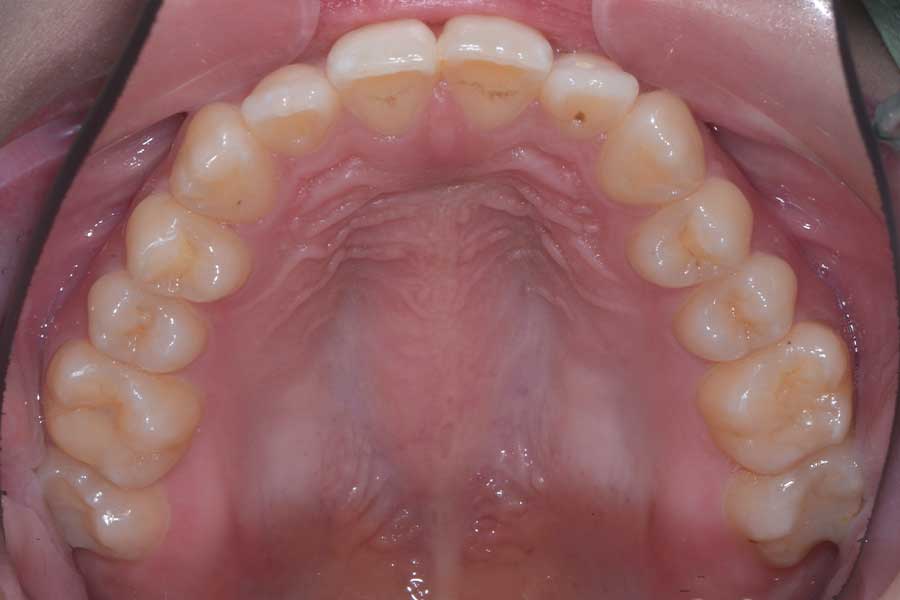

治療前

主訴 前歯で咬み切れるようになりたい

治療内容 ハーフリンガル矯正(上顎裏側・下顎表側矯正)